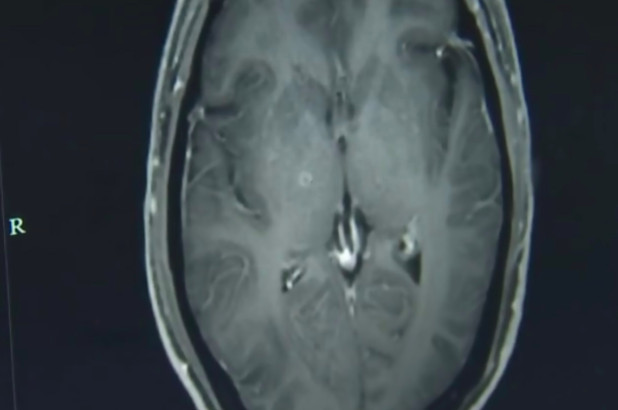

Hình ảnh chụp não cho thấy có hàng trăm con sán cư trú tại đó.

TPO - Một người đàn ông 43 tuổi ở Trung Quốc bị co giật và mất ý thức đã phải nhập viện sau khi các triệu chứng kéo dài trong vài tuần. Các bác sỹ phát hiện ra rằng trong não và ngực của anh ta có hàng trăm con sán dây đang cư trú.

Tiến sỹ Jianrong giải thích rằng, ấu trùng xâm nhập vào cơ thể Zhongfa thông qua đường tiêu hóa và lan truyền qua các mạch máu. Anh ta được chẩn đoán mắc bệnh ấu trùng sán lợn và đau đầu, động kinh vì sán lợn ký sinh trong não và được chỉ định sử dụng một loại thuốc chống ký sinh trùng cùng các loại thuốc khác để bảo vệ các cơ quan khỏi bị tổn thương thêm.